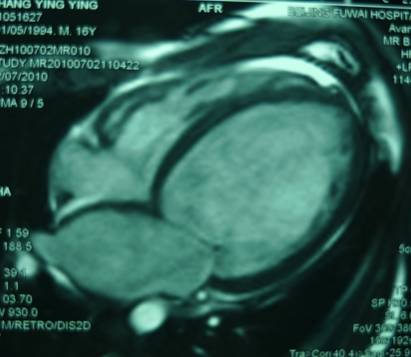

MRI

►左室腔明显扩大,室间隔及左室壁普遍变薄,各节段运动减弱

►心肌延迟强化未见明显异常

►考虑符合扩心病、心衰